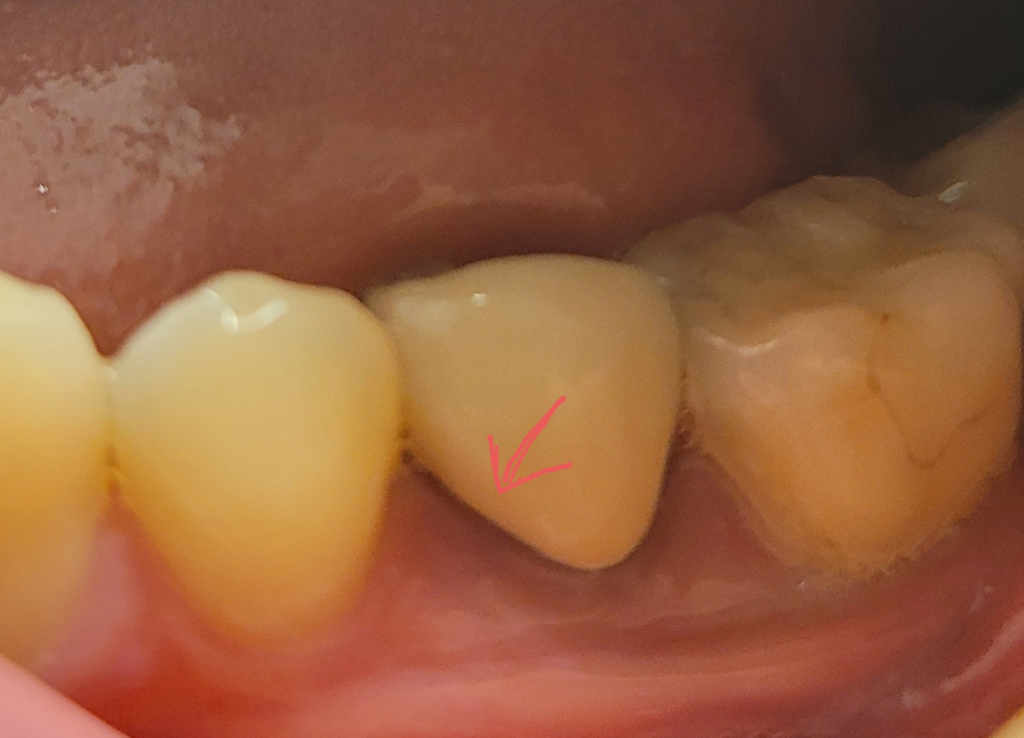

치간칫솔 쓰다가 피가 났습니다.

치간 칫솔을 사용하다가 미끄러져서

잇몸에 지금 표시한 위치에 치간칫솔이 쑤욱 들어갔습니다

사용한 치간칫솔은 이거구요 정확하진 않지만 체감상 저만큼 들어간 것 같습니다.

놀라서 바로 뺐는데 피가 꽤 많이 나더라구요.

그래도 이내 금방 피는 멎었고 지금 특별한 통증은 없고

약간 열감(?) 정도만 있습니다.